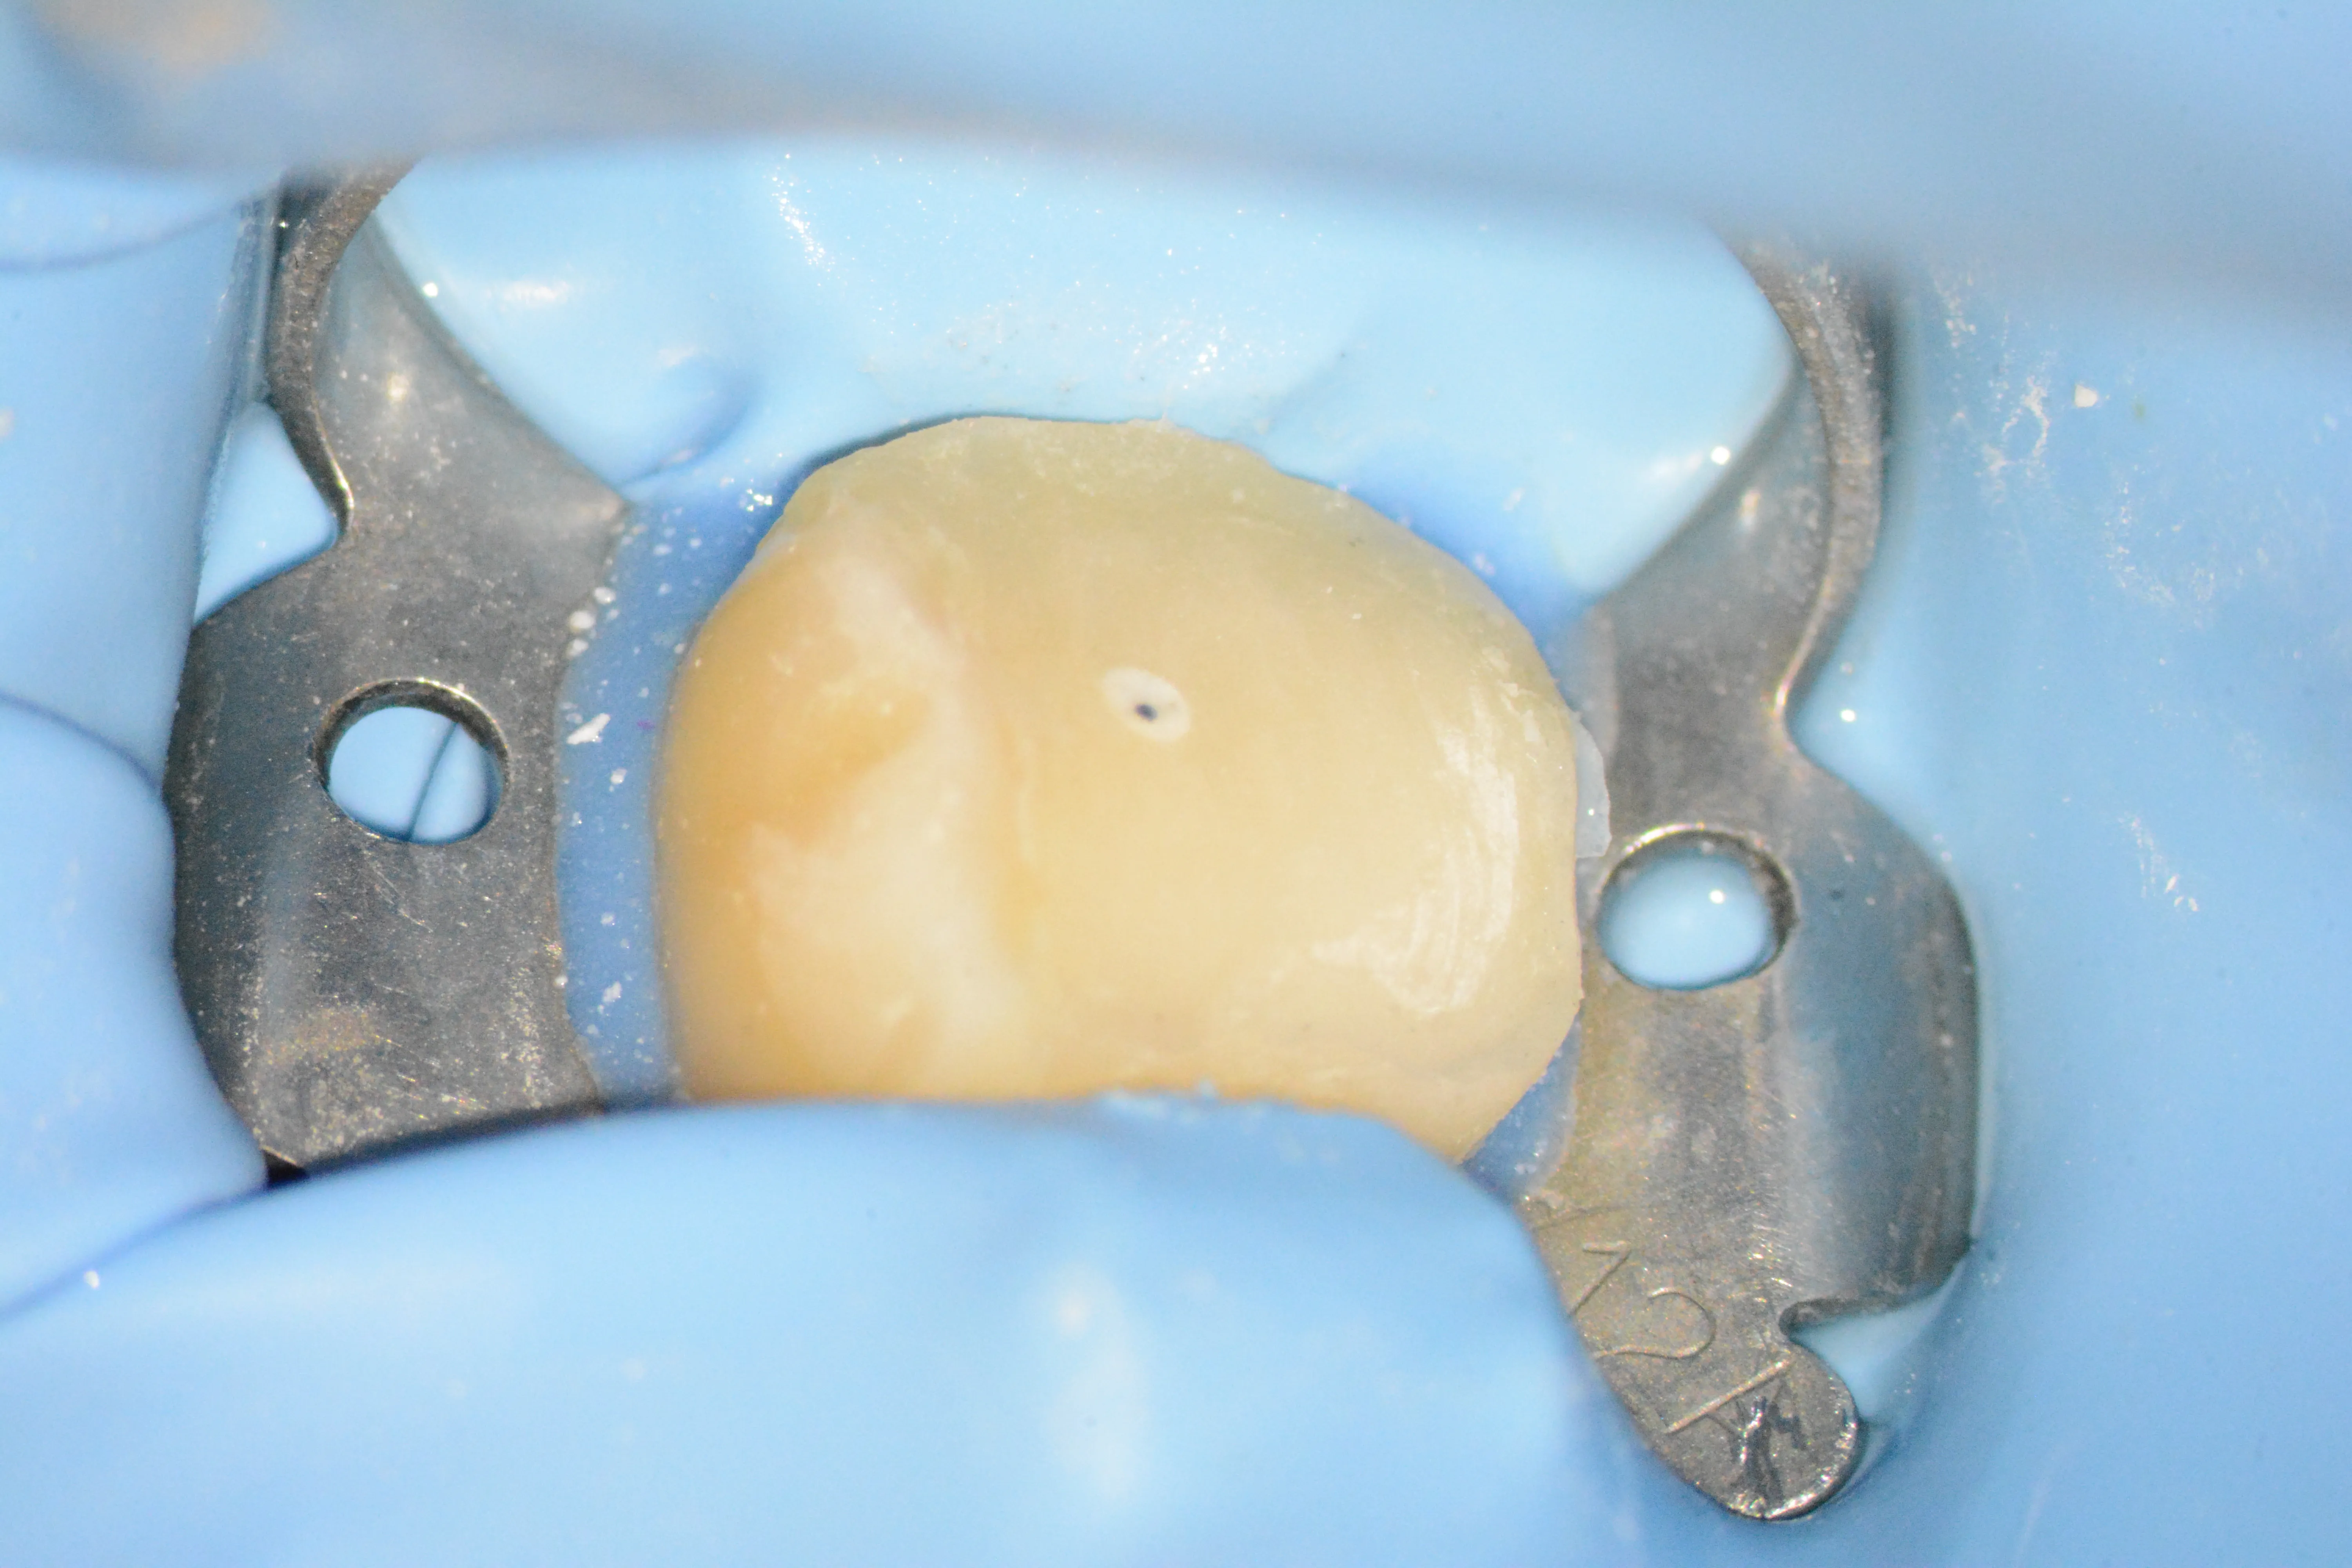

5 – Adaptarea matricei circulare